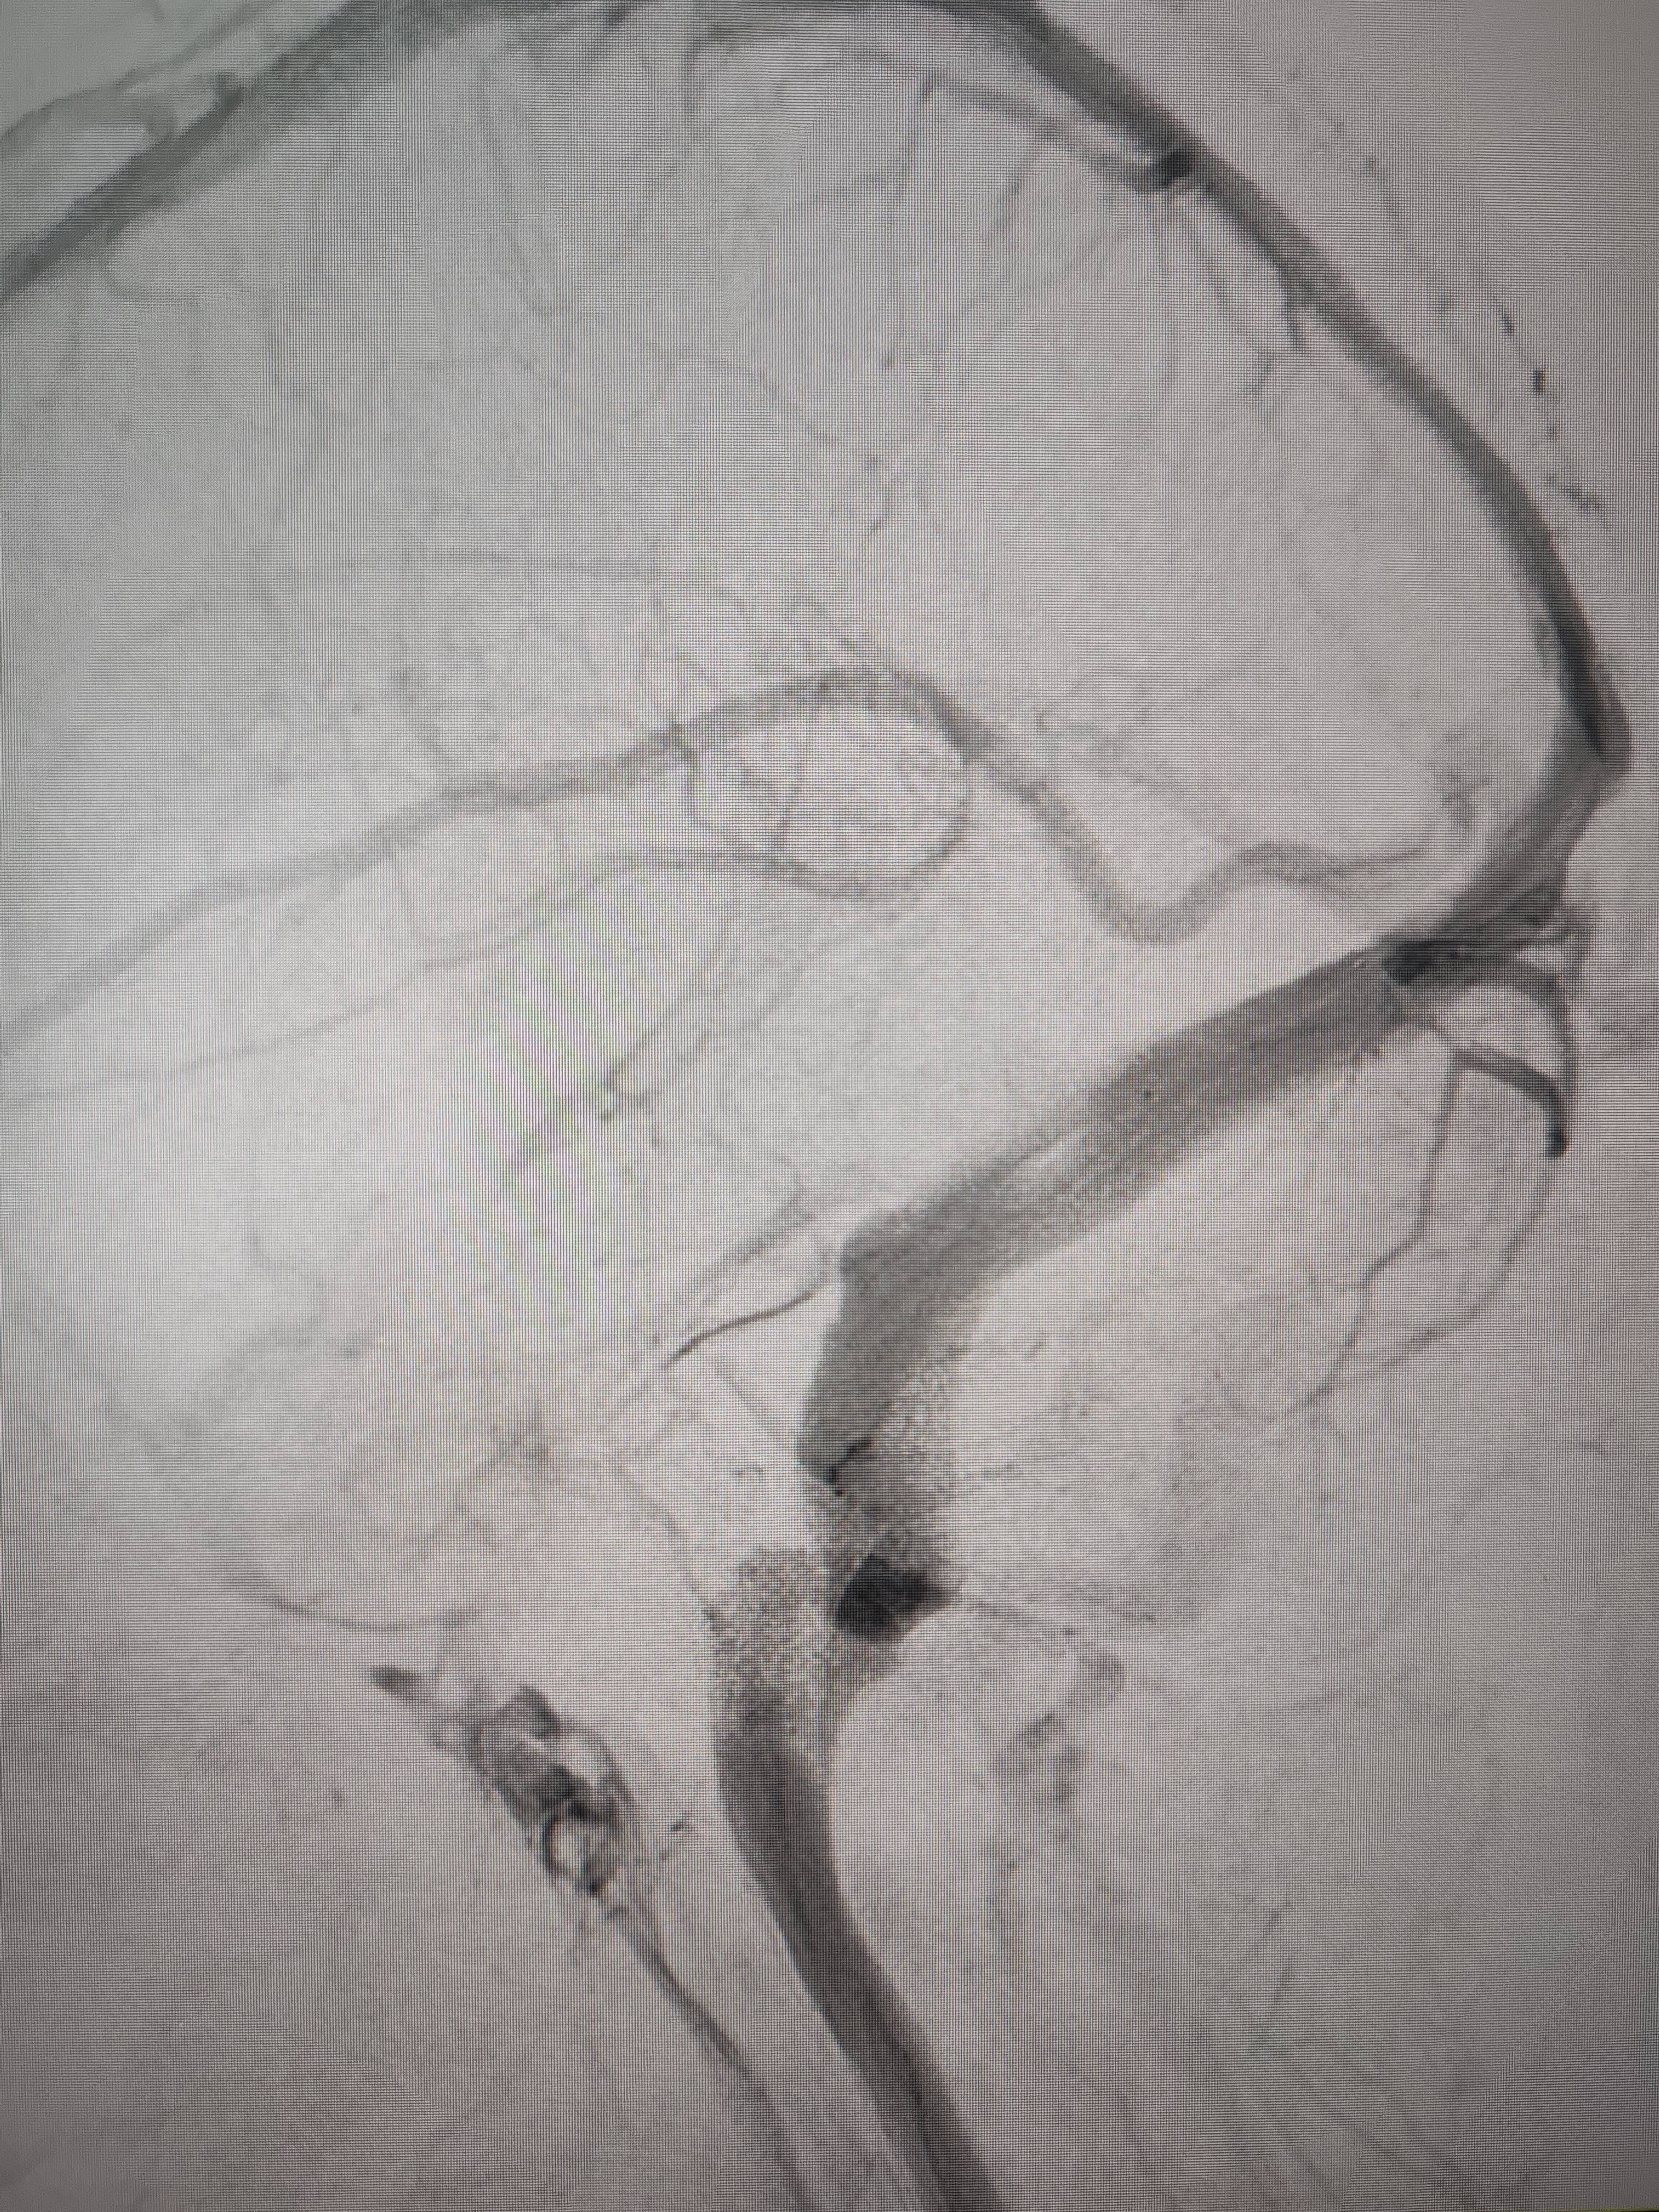

经过静脉窦支架置入手术治疗后,患者的静脉窦“堵点”被打通。 南方+ 欧阳少伟 拍摄